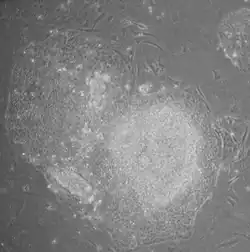

- Uma pequena parcela dessas células transfectadas (0,01-0,1% [25]) ganham características de células-tronco pluripotentes e geram colônias.